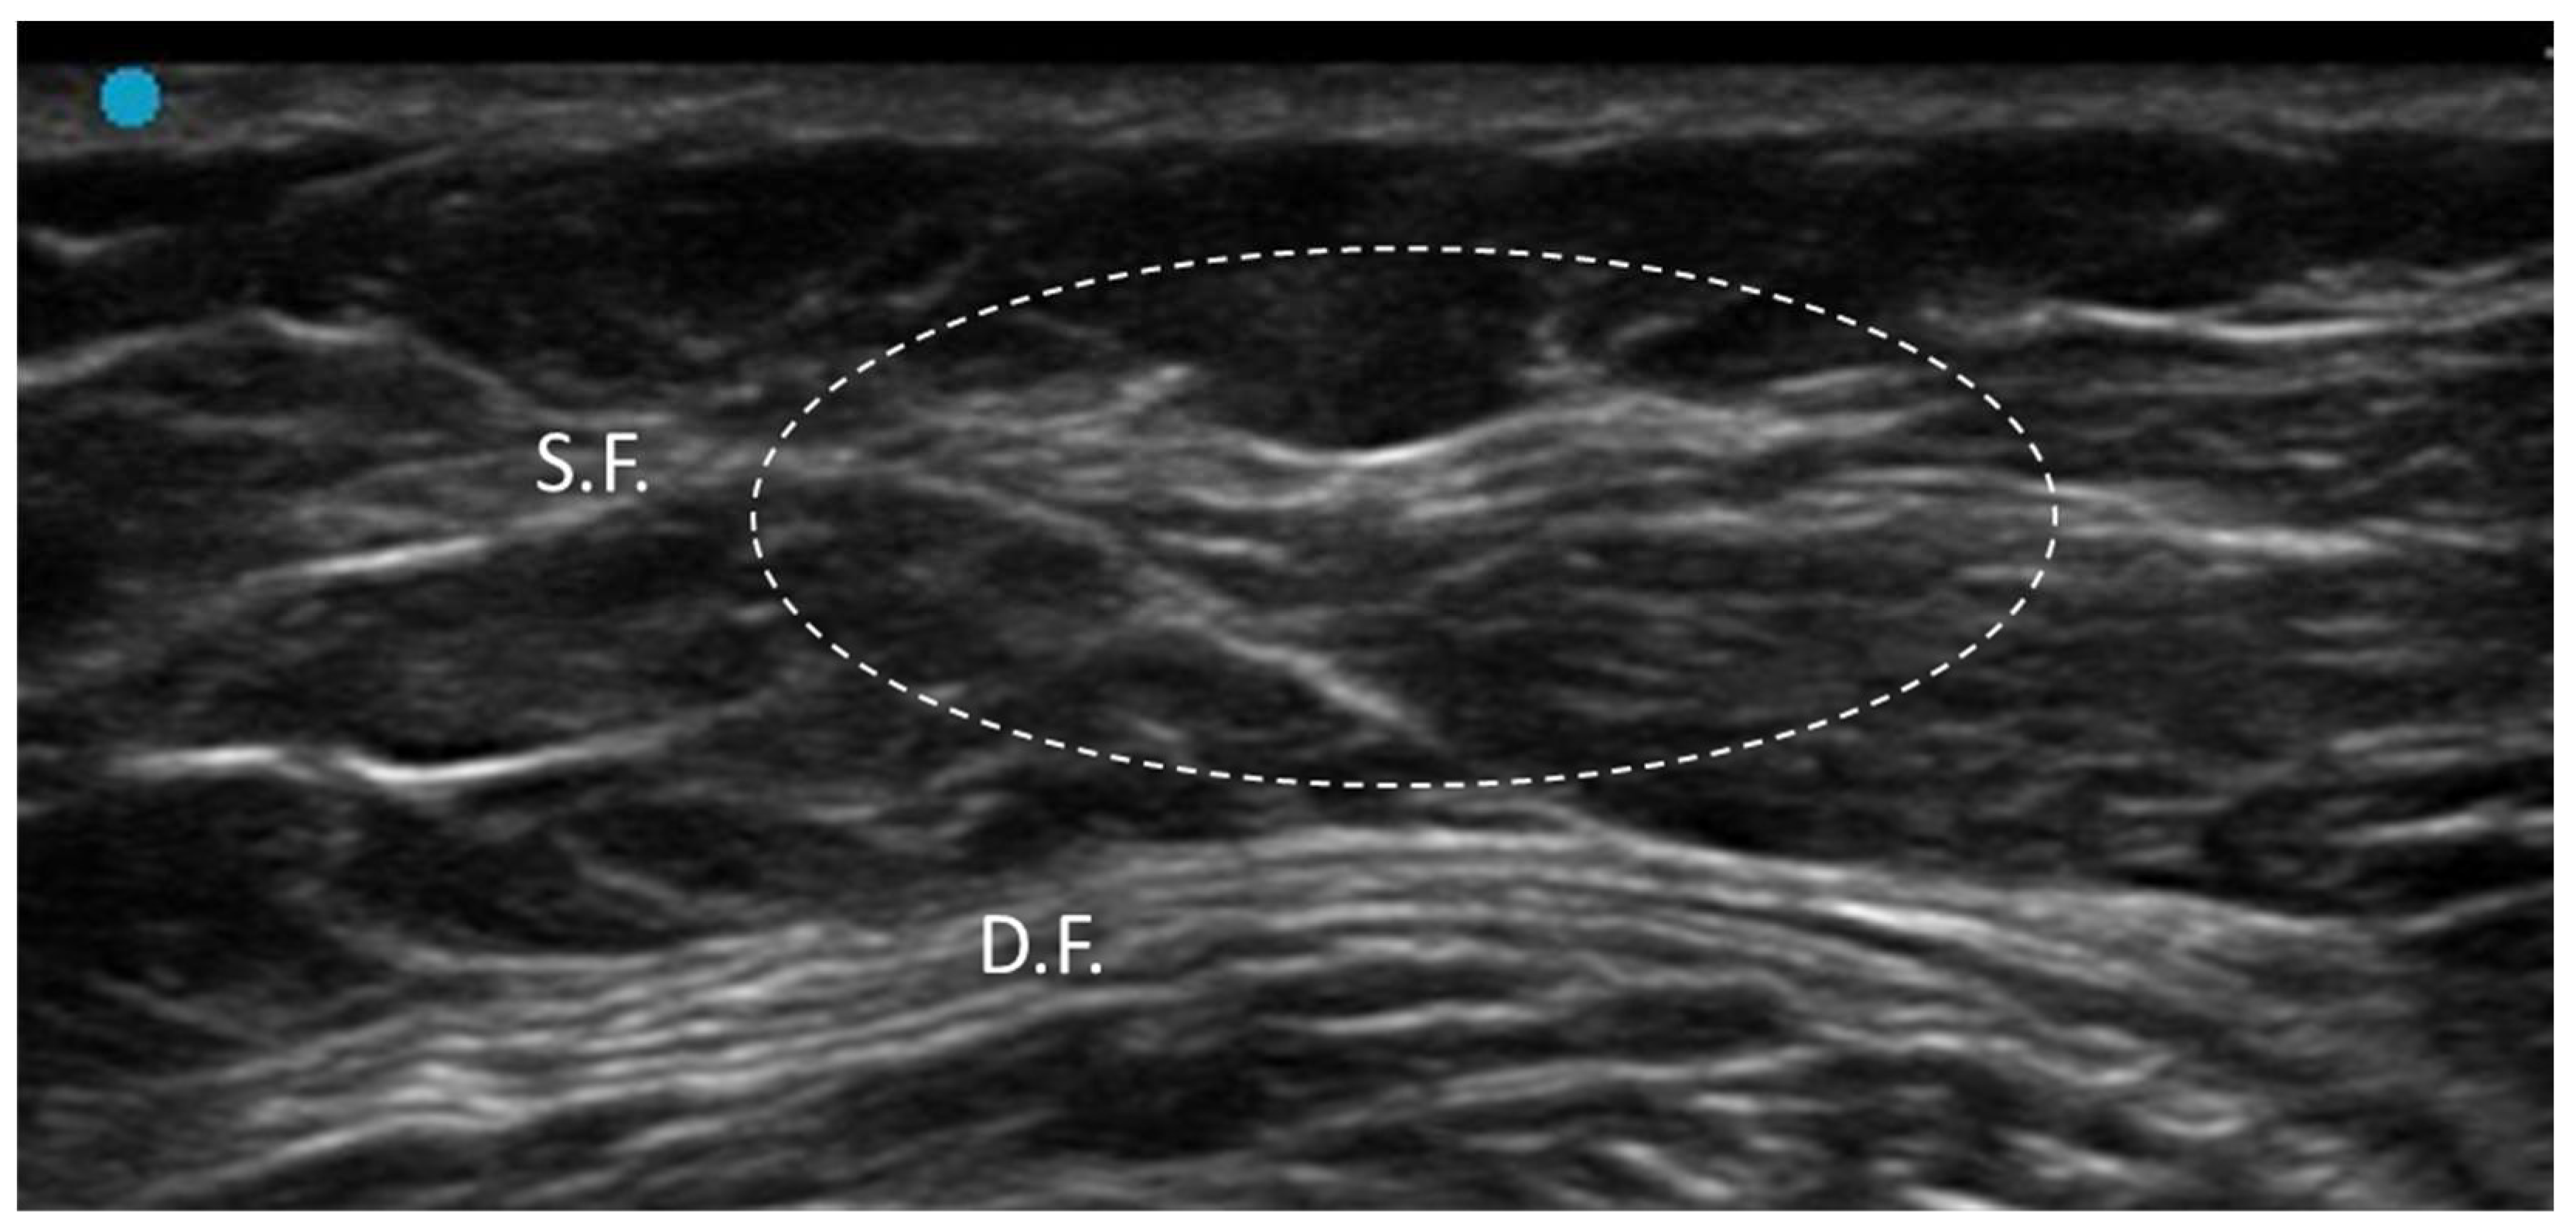

3.1. Normal Ultrasonographic Appearance of Fasciae

3.2.2. Densification